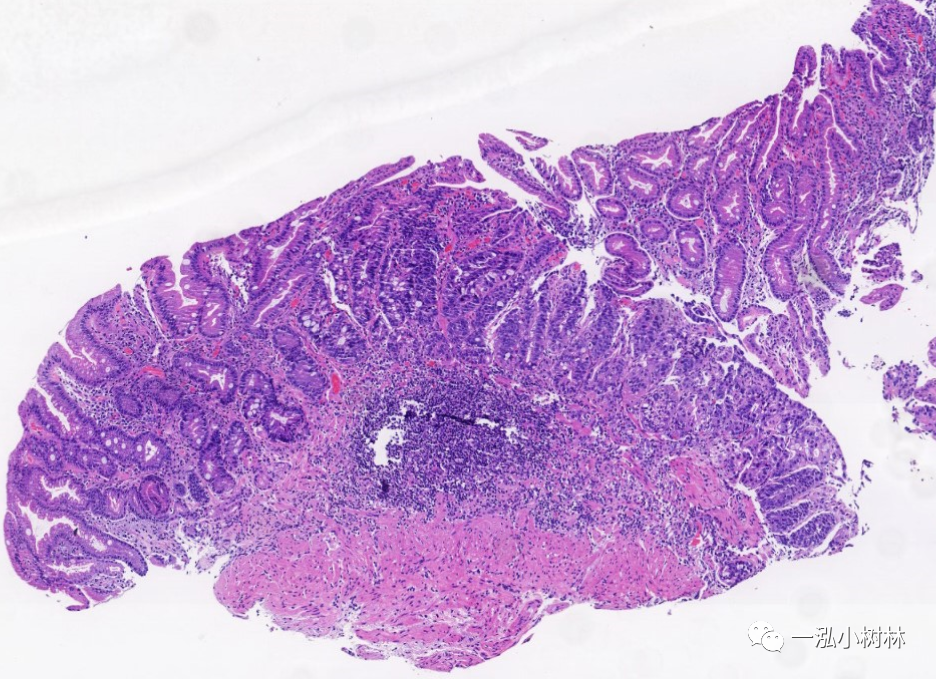

肠化的胃粘膜

图片尺寸936x468